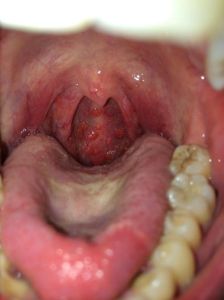

天天得靠嗓门吃饭的人,..老师、销售、歌手最容易中招。声音嘶哑、咳嗽个不停,成了这些人家常便饭。声带小结一出来,唱歌、说话都得小心翼翼,稍微不留神就咳个不停。